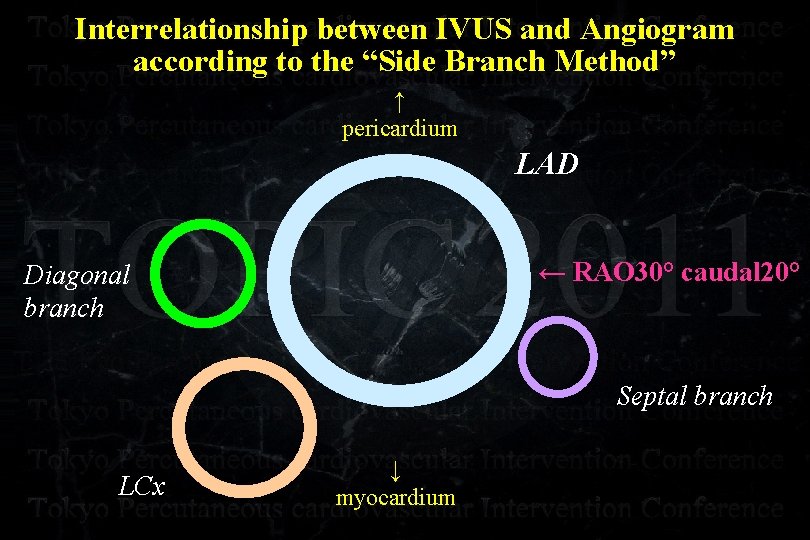

Interrelationship between IVUS and Angiogram according to the “Side Branch Method” ↑ pericardium LAD ← RAO 30° caudal 20° Diagonal branch Septal branch LCx ↓ myocardium